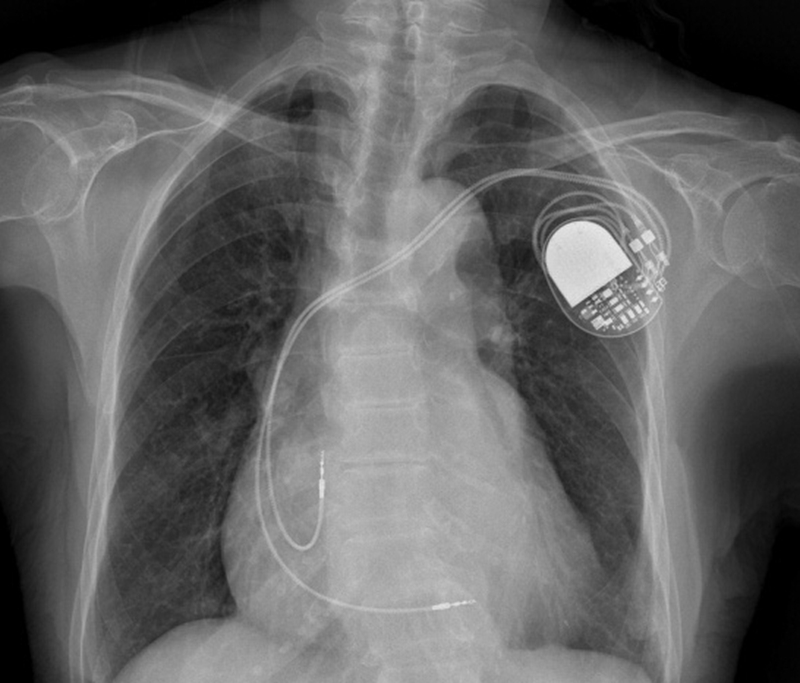

2.心脏起搏器植入术

心脏起搏器植入技术居全省同级医院前列,至今共完成手术400多例,年龄最大的 96岁。开展技术包括单腔永久心脏起搏器植入术, 双腔永久心脏起搏器植入术,心脏复律除颤器(ICD)植入术,同步化起搏除颤器CRT-D更换术,左束支区域心脏永久起搏术。永久心脏起搏术获玉环市首届医 学学科“科技创新奖"新技术组一等奖。